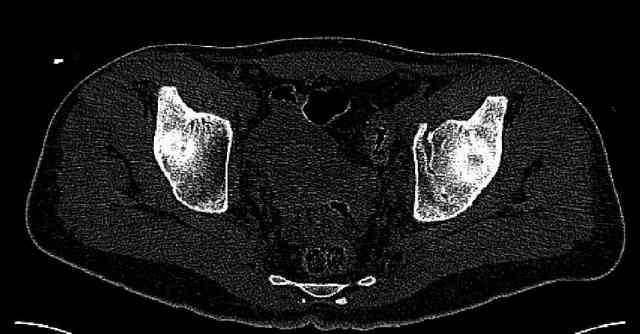

Мужчина 33 лет получил травму в шахте (придавило вагонеткой) 6 недель назад. Изолированное повреждение вертлужной впадины.

В местной больнице отлежал несколько недель на вытяжении. После выписки амбулатрный травматолог направил в институт. На сегодня, похоже, уже имеется неправиильное сращение. См. картинки.

Dear all,A male 23 y.o. injured 6 weeks ago - mine trauma, impacted by a carriage. Isolated injury of the acetabulum. At the initial hosptial was on bed traction some weeks. After discharge visited anotheк orthopaedic surgeon who referred him to our unit. To date looks like a malunion. Images attached. The question is about what to do now - either leave it as is or perform open reduction? If the latter what approach, reduction manoeuvres and fixation would you advice? Thx in advance!

What is your indication for surgical management? What kind of fracture do you think it is? It looks like a transverse type although it has been a couple of years since I looked at an acetabular fracture.

My concern would be that the risk of leaving it malreduced is very high. It appears to be primarily a gap rather than a step in the articular surface. Do you have any CT views that show an articular step?

The last two images from the 3-D CT scan certainly makes the fracture look worse than the plan radiographs.

The joint is non-concentric as the head appears to be either "following the caudal segment", or the dome component is displaced from the tethered head... or so it seems... and he's young... so, many fracture surgeons would recommend reduction and fixation.

Normal appearing SI joints and a healed posterior column limb... my bet's on caudal segment displacement.